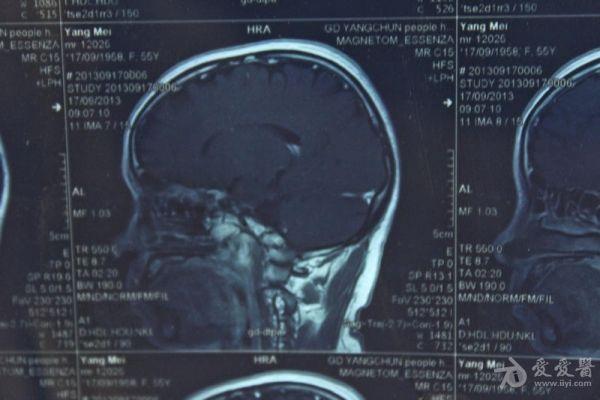

脑部占位病变CT,MRI图片,请帮忙诊断

最近感图样,无其它脑病病史

考虑脑膜瘤!!

磁共振没有平扫,增强矢状位没找到病灶。像脑膜瘤。

图片不是很清楚,应该是脑膜瘤!